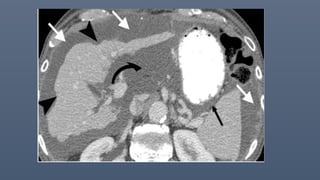

Peritoneal desmoplastic small round cell tumor in a 33-year-old man. Axial contrast-enhanced CT

images of

the abdomen and pelvis show diffuse, irregular, nodular peritoneal thickening (white straight

arrows in A and C), which are most pronounced in the left subphrenic space (black arrowheads in

A), with mild ascites (black straight arrow in A).

Involvement of the peritoneal lining of the falciform ligament (curved black arrows in A and B) and

hepatoduodenal ligament (white arrowheads in B) is noted. Multiple visceral peritoneal and

mesenteric nodules (black arrowheads in C) are noted, with diffuse involvement of the ileal small

bowel mesentery. The tumor is noted to extend into the porta hepatis region (curved white arrow

in B).

Peritoneal desmoplastic smallround cell tumor in a 33-year-old man. Axial contrast-enhanced CT images of the abdomen and pelvis show diffuse, irregular, nodular peritoneal thickening (white straight arrows in A and C), which are most pronounced in the left subphrenic space (black arrowheads in A), with mild ascites (black straight arrow in A). Involvement of the peritoneal lining of the falciform ligament (curved black arrows in A and B) and hepatoduodenal ligament (white arrowheads in B) is noted. Multiple visceral peritoneal and mesenteric nodules (black arrowheads in C) are noted, with diffuse involvement of the ileal small bowel mesentery. The tumor is noted to extend into the porta hepatis region (curved white arrow in B).